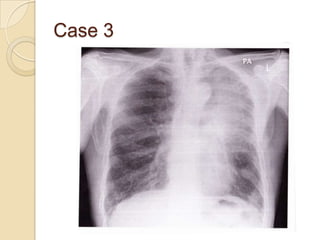

Case 3

   Right lower lobe

collapse

◦ Whiteness

immediately above

the diaphragm (1)

causing loss of its

outline

◦ Right heart border

maintained

Case 3  Right lower lobe collapse ◦ Whiteness immediately above the diaphragm (1) causing loss of its outline ◦ Right heart border maintained